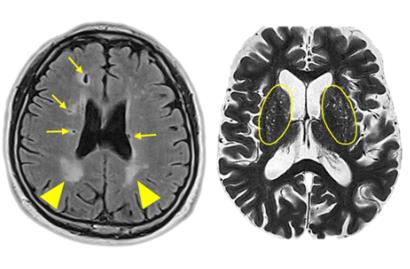

뇌백질 고신호 병변(좌측 사진 화살촉), 열공성 뇌경색(좌측 사진 화살표), 확장성 혈관주위 공간(우측 사진 양쪽 타원 안쪽의 하얀 점들)이 나타난 뇌 MRI 사진

그 결과 호모시스테인 농도가 높은 그룹에서는 혈관 미세출혈과 ‘뇌백질 고신호'(MRI상의 진한 흰색 병변), ‘열공성 뇌경색’(증상이 없는 뇌졸중 증상) 비율이 높았다.

또 전체의 14%에서는 혈관 주변에 빈 공간이 많아 뇌 조직이 치밀하게 자리 잡지 못한 것으로 볼 수 있는 ‘확장성 혈관주위 공간’(EPVS)을 25개 이상 가지고 있었다. 특히 정상 범위로 알려진 호모시스테인 농도(5∼15μmol/ℓ)에서도 뇌경색 위험이 높아지는 유의성이 발견됐다고 연구팀은 강조했다.